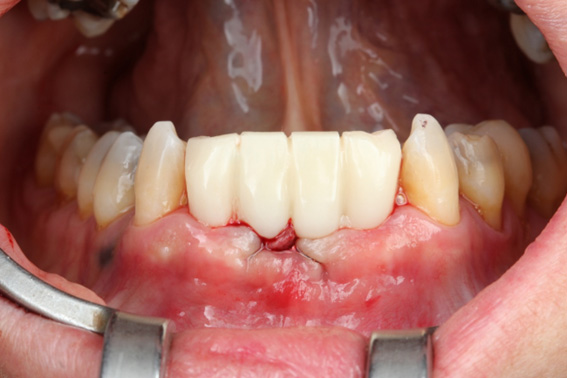

1 | Initial aspect, teeth in occlusion

2 | Initial aspect, lower elements